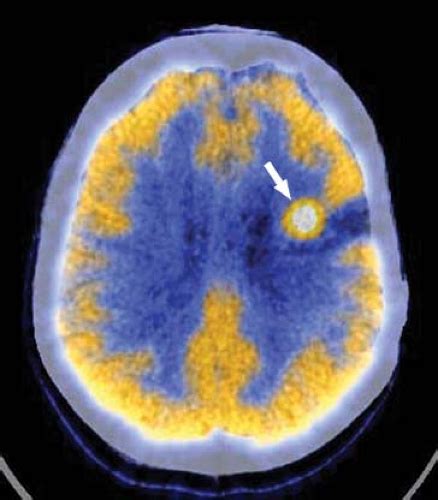

Thyroid nodule - autonomous | Image | Radiopaedia.org

Thyroid nodule - autonomous | Image | Radiopaedia.org from images.radiopaedia.org